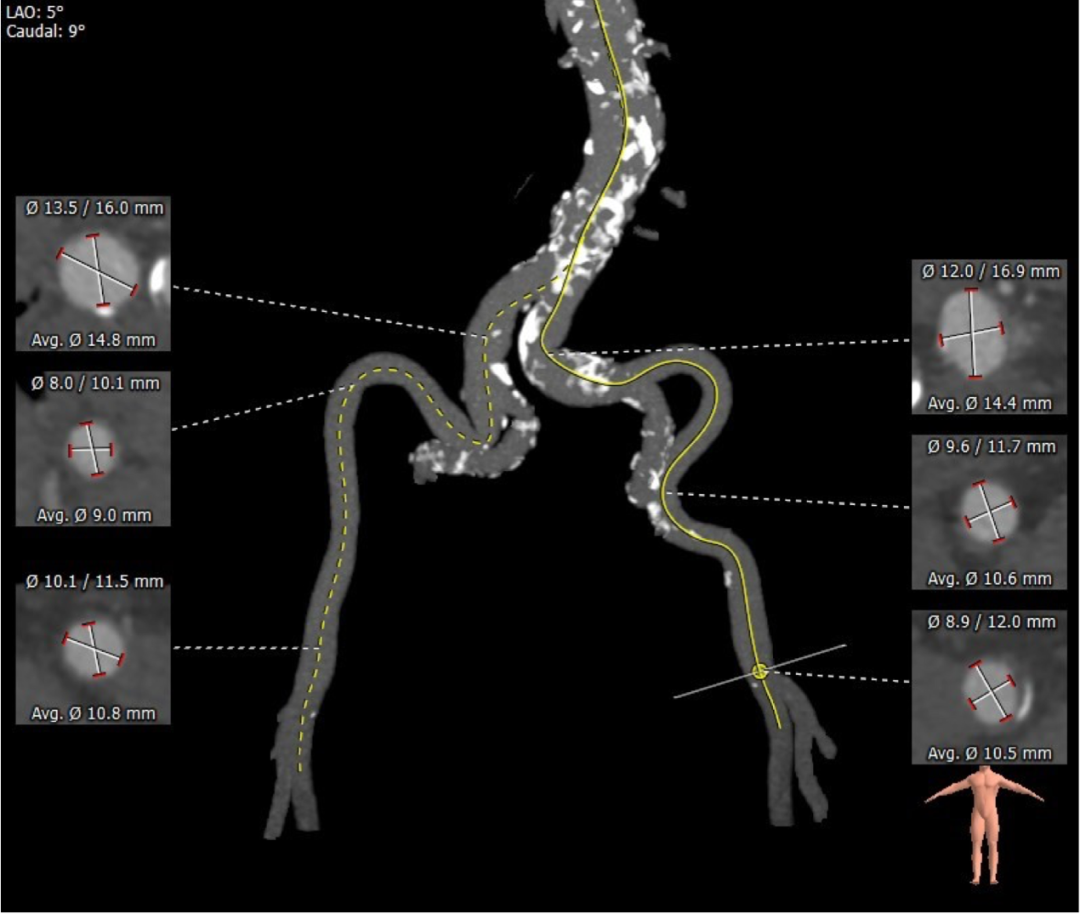

血管外周入路评估:

2022年01月11日,厦门大学附属心血管病医院王焱教授领衔的结构性心脏病团队顺利完成由沛嘉医疗自主研发的TaurusNXT“非醛交联”经导管主动脉瓣系统(干瓣预装载)临床试验分中心首例植入。患者为三叶式主动脉瓣,瓣叶轻度钙化,左右冠开口钙化严重,双侧入路血管严重迂曲。手术在麻醉科、超声科、心外科的大力支持下,由王焱教授、王斌教授、陈翔教授首先实施冠脉介入(PCI)治疗,随后实施经导管主动脉瓣置换(TAVR)手术,一站式手术一气呵成,经过顺利,手术取得圆满成功。手术后患者状态良好,血流动力学均得到显著改善。